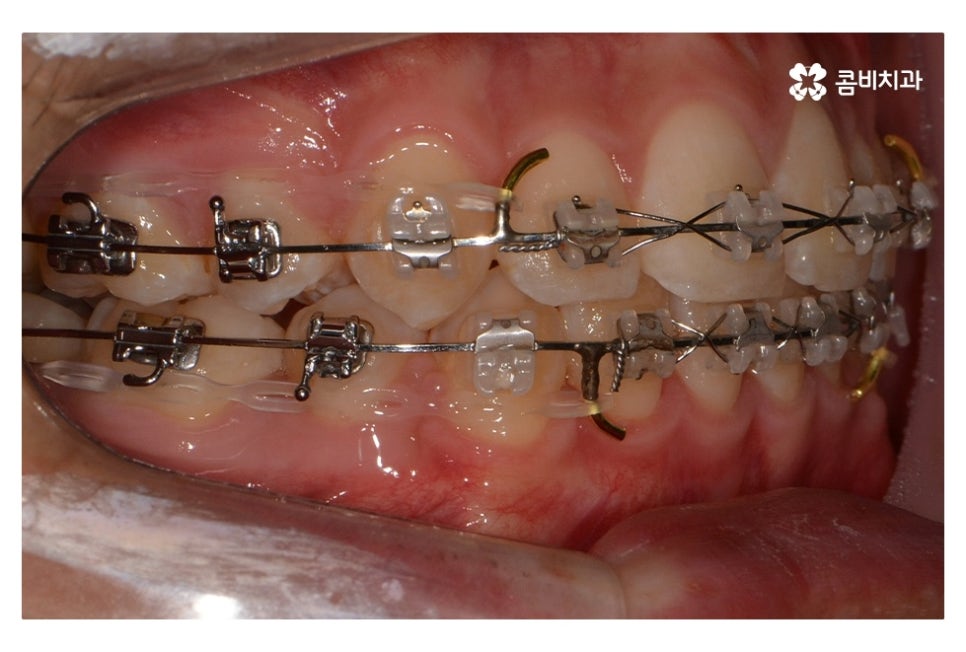

오늘 보여드릴 중학생치아교정 사례의 경우에는

악골의 위치는 정상적인 상태에서 불규칙한 치열로 인해

교정 치료를 진행한 사례라고 할 수 있어요.

위 환자분의 경우 발치가 진행된 사례로 치아의 이동 공간을

고려할 때 발치가 필요했고 환자분도 보다 나은

심미성을 위해서 동의한 상황이라고 할 수 있어요.

위 사진에서 보시면 시간이 지나면서 발치를 했던 치아의

공간이 사라지고 교정을 통해서 치열이 가지런해진 것을 확인할 수 있는데요.

중학생치아교정에 있어서 중요한 사항이 단지 치열만이

가지런해 보이는 것이 아닌 얼굴과의 조화와 교합이라 할 수 있어요.